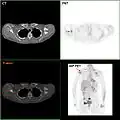

High-grade invasive ductal carcinoma, with minimal tubule formation, marked pleomorphism, and prominent mitoses, 40x field -

F-18 FDG PET/CT: A breast cancer metastasis to the right scapula